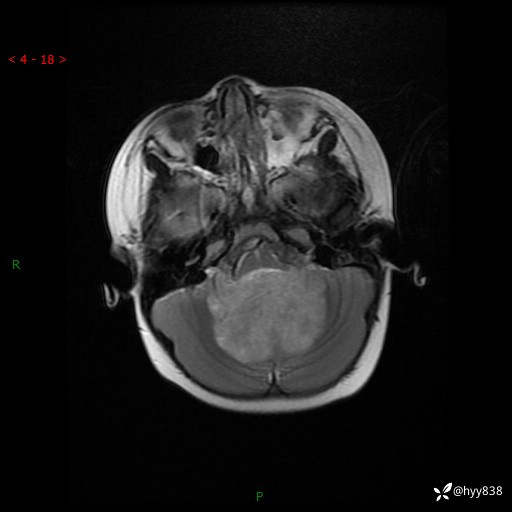

理解“经典”,从经典病例开始,3岁小女孩,行走不稳2个月,加重1个月--结果公布

性别:女

年龄:3岁

简要病史:发现行走不稳2个月,加重1个月

颅脑MRI平扫+增强

三脑室、四脑室多发病变,如何分析?